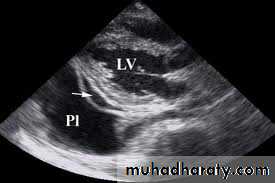

-Ultrasonography is more accurate than plain chest radiography for determining the volume of pleural fluid and frequently provides additional helpful information.

Visualization of fluid facilitates skin marking to indicate a site for safe needle aspiration and guides pleural biopsy, increasing diagnostic yield